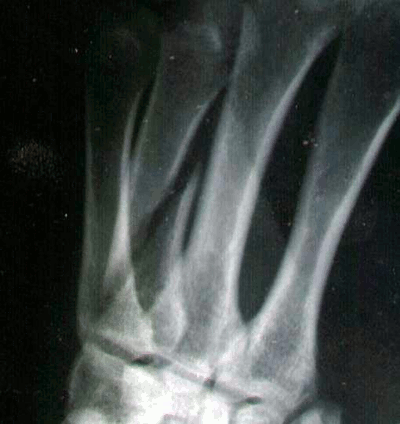

| Hätten Sie es erkannt? | |